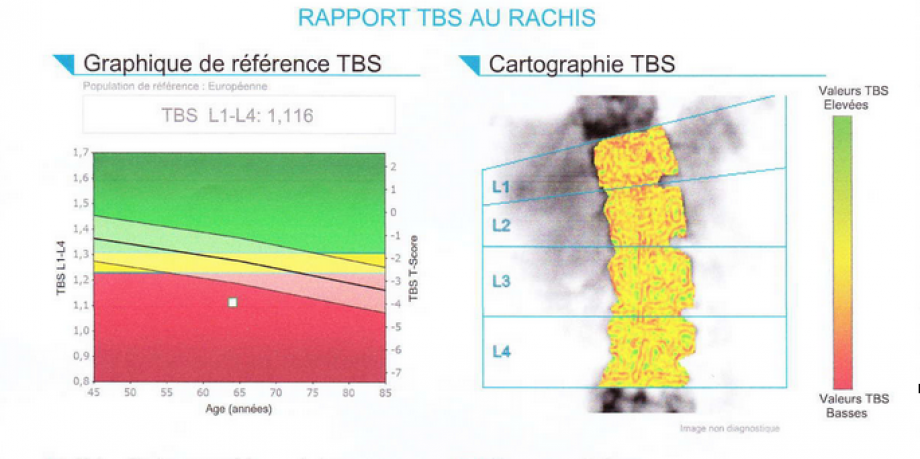

Ostéodensitométrie

ou densitométrie osseuse